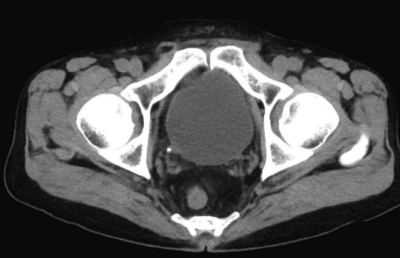

尿所見:蛋白(-)、糖(-)、潜血3+、沈渣に赤血球 100 以上/1視野、正八面体の結晶を認める。血液所見:赤血球 458 万、Hb 14.0 g/dL、Ht 45 %、白血球 9,300、血小板 21 万。血液生化学所見:総蛋白 7.2 g/dL、アルブミン 3.7 g/dL、総ビリルビン 0.9 mg/dL、直接ビリルビン 0.2 mg/dL、 AST 35 U/L、ALT 32 U/L、LD 179 U/L(基準 176〜353)、尿素窒素 22 mg/dL、クレアチニン 1.2 mg/dL、尿酸 6.9 mg/dL、血糖 98 mg/dL、Na 132 mEq/L、K 4.3 mEq/L、Cl 97 mEq/L、Ca 9.1 mg/dL。非ステロイド性抗炎症薬が投与され痛は軽減した。その後に撮影した腹部CT を示す。